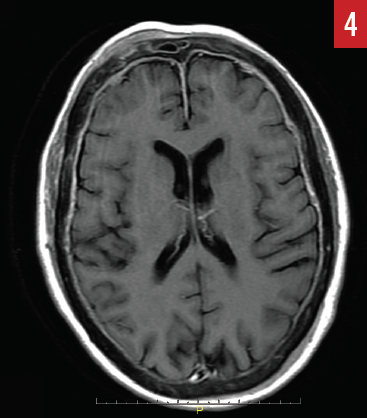

MR imaging of the brain (Figures 4 and 5) identified diffuse epidural enhancement, as well as enhancement in the right internal auditory canal. Inasmuch as this patient was on low-dose prednisone for temporal arteritis, intratympanic steroid treatment was utilized but brought about no improvement in hearing acuity.

Figure 4. Axial MR image identifies diffuse epidural enhancement along with convexities that represent direct epidural extension from calvarial metastatic disease (case report 2).